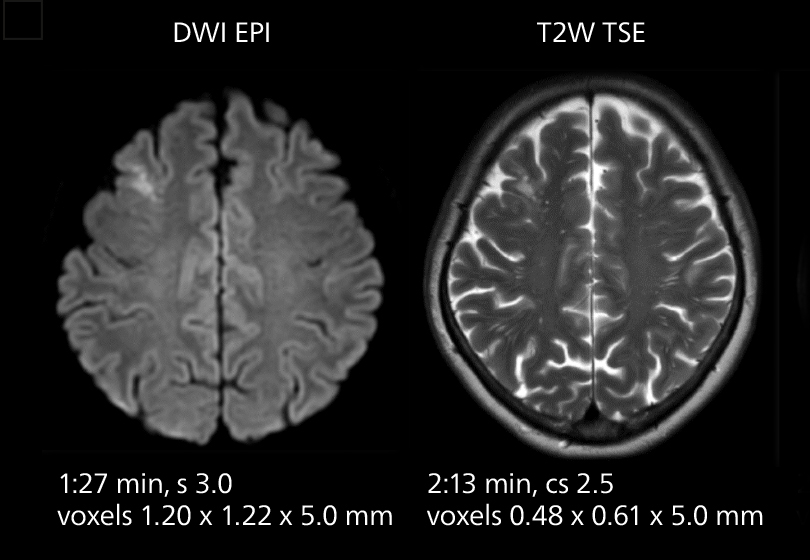

These images of an old cerebral infarction demonstrate the speed and image quality after upgrading to Elition X.